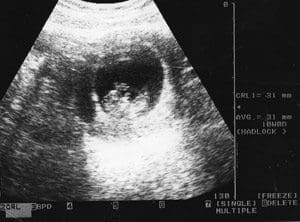

It’s a bit blurry, but you can see his tiny head, arms and body on the ultrasound as he grew inside Mareza.

That was actually the second image of Joseph that Mareza had taken that February day in 2011, and it’s the one that convinced her that Joseph was a person, a life waiting to be born, instead of a blob of tissue that she had planned on aborting.

“Those words were with her for the rest of her visit and he was right. There is another person here,” explained Irma Landeros of her daughter’s reaction to Miller’s comment.USEsscans110-B2-CopyMareza Landeros had two ultrasounds performed on her on Feb. 24, 2011 when she was about 10 weeks pregnant. The first, performed at Affiliated Medical Services, Milwaukee, an abortion clinic, is at top. Its wide angle image makes it difficult to distinguish features of the unborn baby. Later the same day, the second image was taken at the Women’s Care Center, located across the street. Its more focused image shows distinctive features and limbs of the unborn child.

For the second time that day, Mareza had an ultrasound, and this time, with the closer image, could see the tiny features of her son.

The news devastated Irma who dreamed of a church wedding for her only daughter. Through anger, disbelief and tears, Mareza showed her mother the two ultrasound images and said that even though the baby was only 10 weeks along, he had a heartbeat of 175.